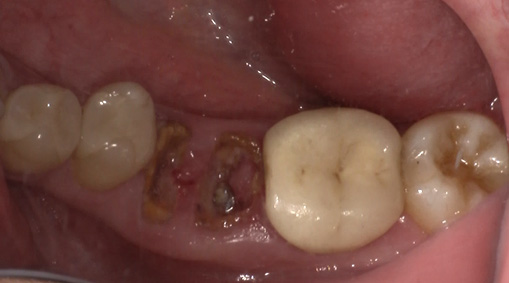

3日目:歯牙移植術を行います。

抜歯する歯の周囲に麻酔をします。

傷んだ歯を抜歯します。

親しらずを抜歯して、移植します。

歯の固定や傷口を縫合します。

術後4週目の移植した歯牙。固定は維持されている。